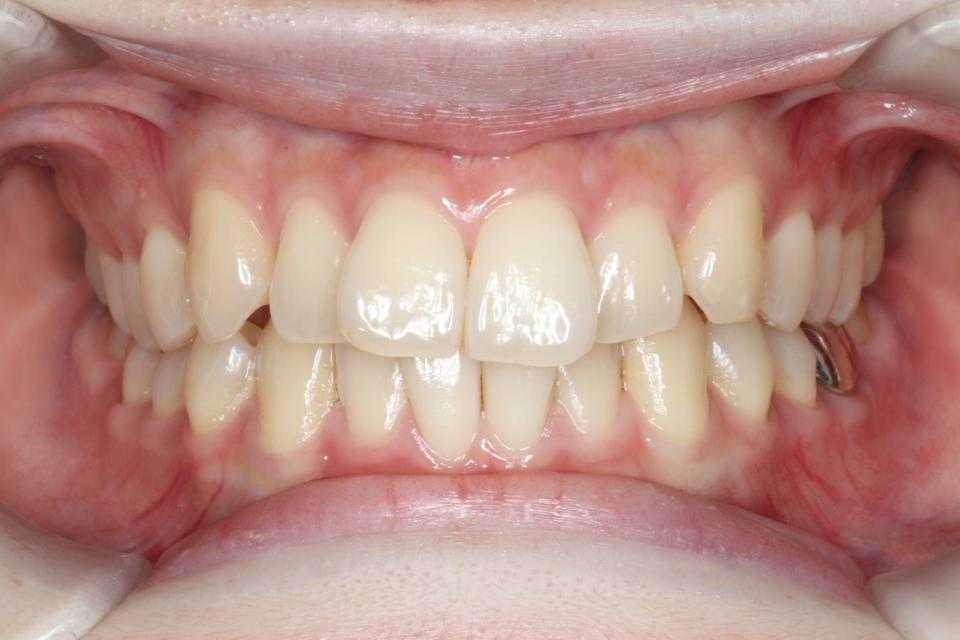

矯正治療前

20代女性です。

上の前歯が2本出ているのが気になると当院に来院されました。

部分的な矯正を希望され、

奥歯の嚙み合わせにも大きな異常はなかったため、

取り外し可能なマウスピース矯正で治療をおこないました。